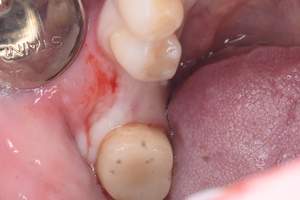

インプラント治療の症例1

症例写真-1

- Befor

- After

症例写真-2

- 途中経過

| 年齢 | 50代・男性 |

| 主訴 | 右下歯が疼く |

| 治療内容 | ・右下6番インプラント ※1:FGG(遊離歯肉移植術)とは、足りない歯ぐきを上顎から上皮を切り取り移植する外科手術 |

| 治療費 | 合計:902,000円(税込) ■内訳 |

| 治療期間 | 9ヵ月 |

| 治療方針 | 右下の当該歯は歯根破折により保存不可能と診断しました。歯周疾患も伴っていたため抜歯後に骨吸収※1が大きく起こることが予測できました。チタンメッシュ併用骨再生誘導法(GBR※2)を選択しインプラント埋入と同時に行い自然な歯槽骨のラインを再現しました。またGBRを行う際にインプラント辺縁の付着歯肉の減少が起こる為、遊離歯肉移植術(FGG※3)を行い清掃性を考慮した形態に仕上げました。 ■治療方針の解説 治療した右下の歯をレントゲンで撮影したところ根本の部分に黒く写る箇所があり「根尖性慢性周囲炎※1」と診断。また歯周病も進行していました。 ※1 骨吸収・・・歯槽骨という歯を支える骨がなくなっていくこと |

| 担当者所見 | 主訴の右下だけでなく歯茎の腫れ、発赤があり不良補綴や不良充填など他にも治療箇所が多数ありました。プラークコントロールが不良であった為まずはブラッシング指導を行いセルフケアの重要性を理解していただくところからスタートしました。 右下6番の歯はインプラント治療を行なった結果審美的にも機能的にも患者様の満足を得ることができました。骨造成と歯肉移植も行なった為インプラントを支える十分な歯周組織の獲得ができたと思っております。 |